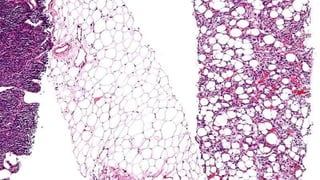

Tumour composed of

lobules of adipose

tissue containing

lipoblasts suggesting

well-differentiated

liposarcoma. Highly

pleomorphic

lipoblasts (inset) were

also seen (H and E,

×10 and ×40)

Tumour composed of lobulesof adipose tissue containing lipoblasts suggesting well-differentiated liposarcoma. Highly pleomorphic lipoblasts (inset) were also seen (H and E, ×10 and ×40)